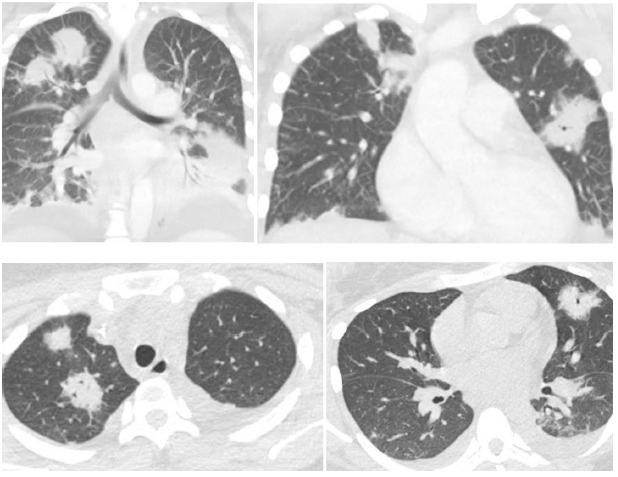

一篇文献报道,一例Lemierre综合征患者的胸部CT显示多发肺脓肿,外周带为主;双侧胸腔积液、脓胸,肺实变。该病例的病原菌为坏死梭杆菌。

图片

图片来源:Respir Med Case Rep, 2019, 28:100867.

我院23岁男性患者,出现咽痛、咳嗽、咳痰5天,发热伴身目黄染4天。3月2日,咽痛,化脓性扁桃体炎;3月6日,双肺结节并空洞;3月13日,双肺结节并空洞+双侧胸腔积液。